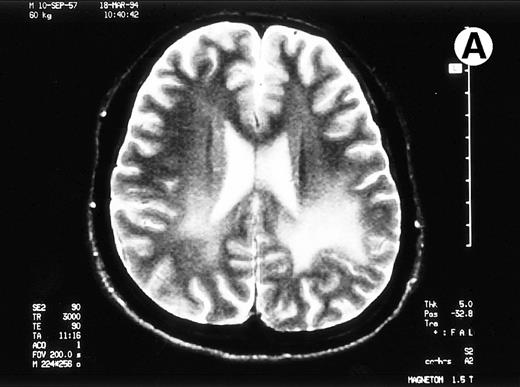

A 35-year-old man with a chronic myelocytic leukemia in a first chronic phase received an allo-BMT prepared for cyclophosphamide 120 mg/kg and total body irradiation 12 Gy from an HLA-identical sibling in October 1992. Acute GVHD developed in grade III and progressed to an extensive chronic GVHD (cGVHD), which included lichenoid lesions of buccal mucosa, oral dryness, keratoconjunctivitis sicca, and hypolacrimation in addition to skin lesion and liver dysfunction. We treated his cGVHD with 150 mg/d of cyclosporine (CsA) and 10 mg/d of prednisolone (PSL). With dose reduction of CsA from 12 months after allo-BMT, his cGVHD gradually deteriorated. Abrupt seizures, lasting a few minutes, developed on day 491 and day 496 when the patient received 100 mg/d of CsA and 10 mg/d of PSL. Neurological examination revealed no abnormalities. MRI detected the pathes of blight signal on T2-weighted method in white matter of brain adjacent bilateral posterior lateral ventricles (Fig 1A). The eloctroencephalogram revealed epileptic abnormal δ and θ waves on left frontal to central lobe. An examination of cerebrospinal fluid (CSF) revealed as follows: an initial pressure 120 mm H2O, protein 98 mg/dL, sugar 55 mg/dL, chrolide 123 mmol/L, cell count 38/μL with all lymphocytes and negative results in antibodies for cytomegalovirus, herpes simplex virus type-1, and toxoplasma. The concentration of interferon-γ was 0.3 U/L in serum and 1.0 U/L in CSF, which measured by radioimmunoassay kit (Medgenics, Belgium).

Paths of blight signal on T2-weighted MRI in white matter of brain adjacent bilateral posterior lateral ventricles. (A) On day 526 when we just withheld cyclosporine. (B) On day 698 when chronic GVHD resolved by readministration of cyclosporine.

To rule out the possibility of CsA neurotoxicity, although the trough levels of CsA ranged from 130 to 170 ng/mL, we withheld CsA at day 526. Despite this attempt, the CNS lesions on MRI did not change, and we subsequently restarted 150 mg/d of CsA at day 537. Thereafter, the CNS lesions gradually resolved with 150 mg/d of CsA and 10 to 20 mg/d of PSL (Fig 1B), coinsident with resolution on the other signs of cGVHD. The seizures never recurred with 600 mg/d of sodium valproate. The patient has now minor CNS lesion and mild signs of cGVHD with 100 mg/d of CsA and with 90% of Karnovsky score at 62 months following allo-BMT.